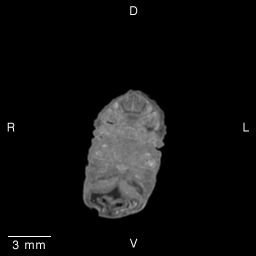

Stage 19 (Day 47), transverse slice 13